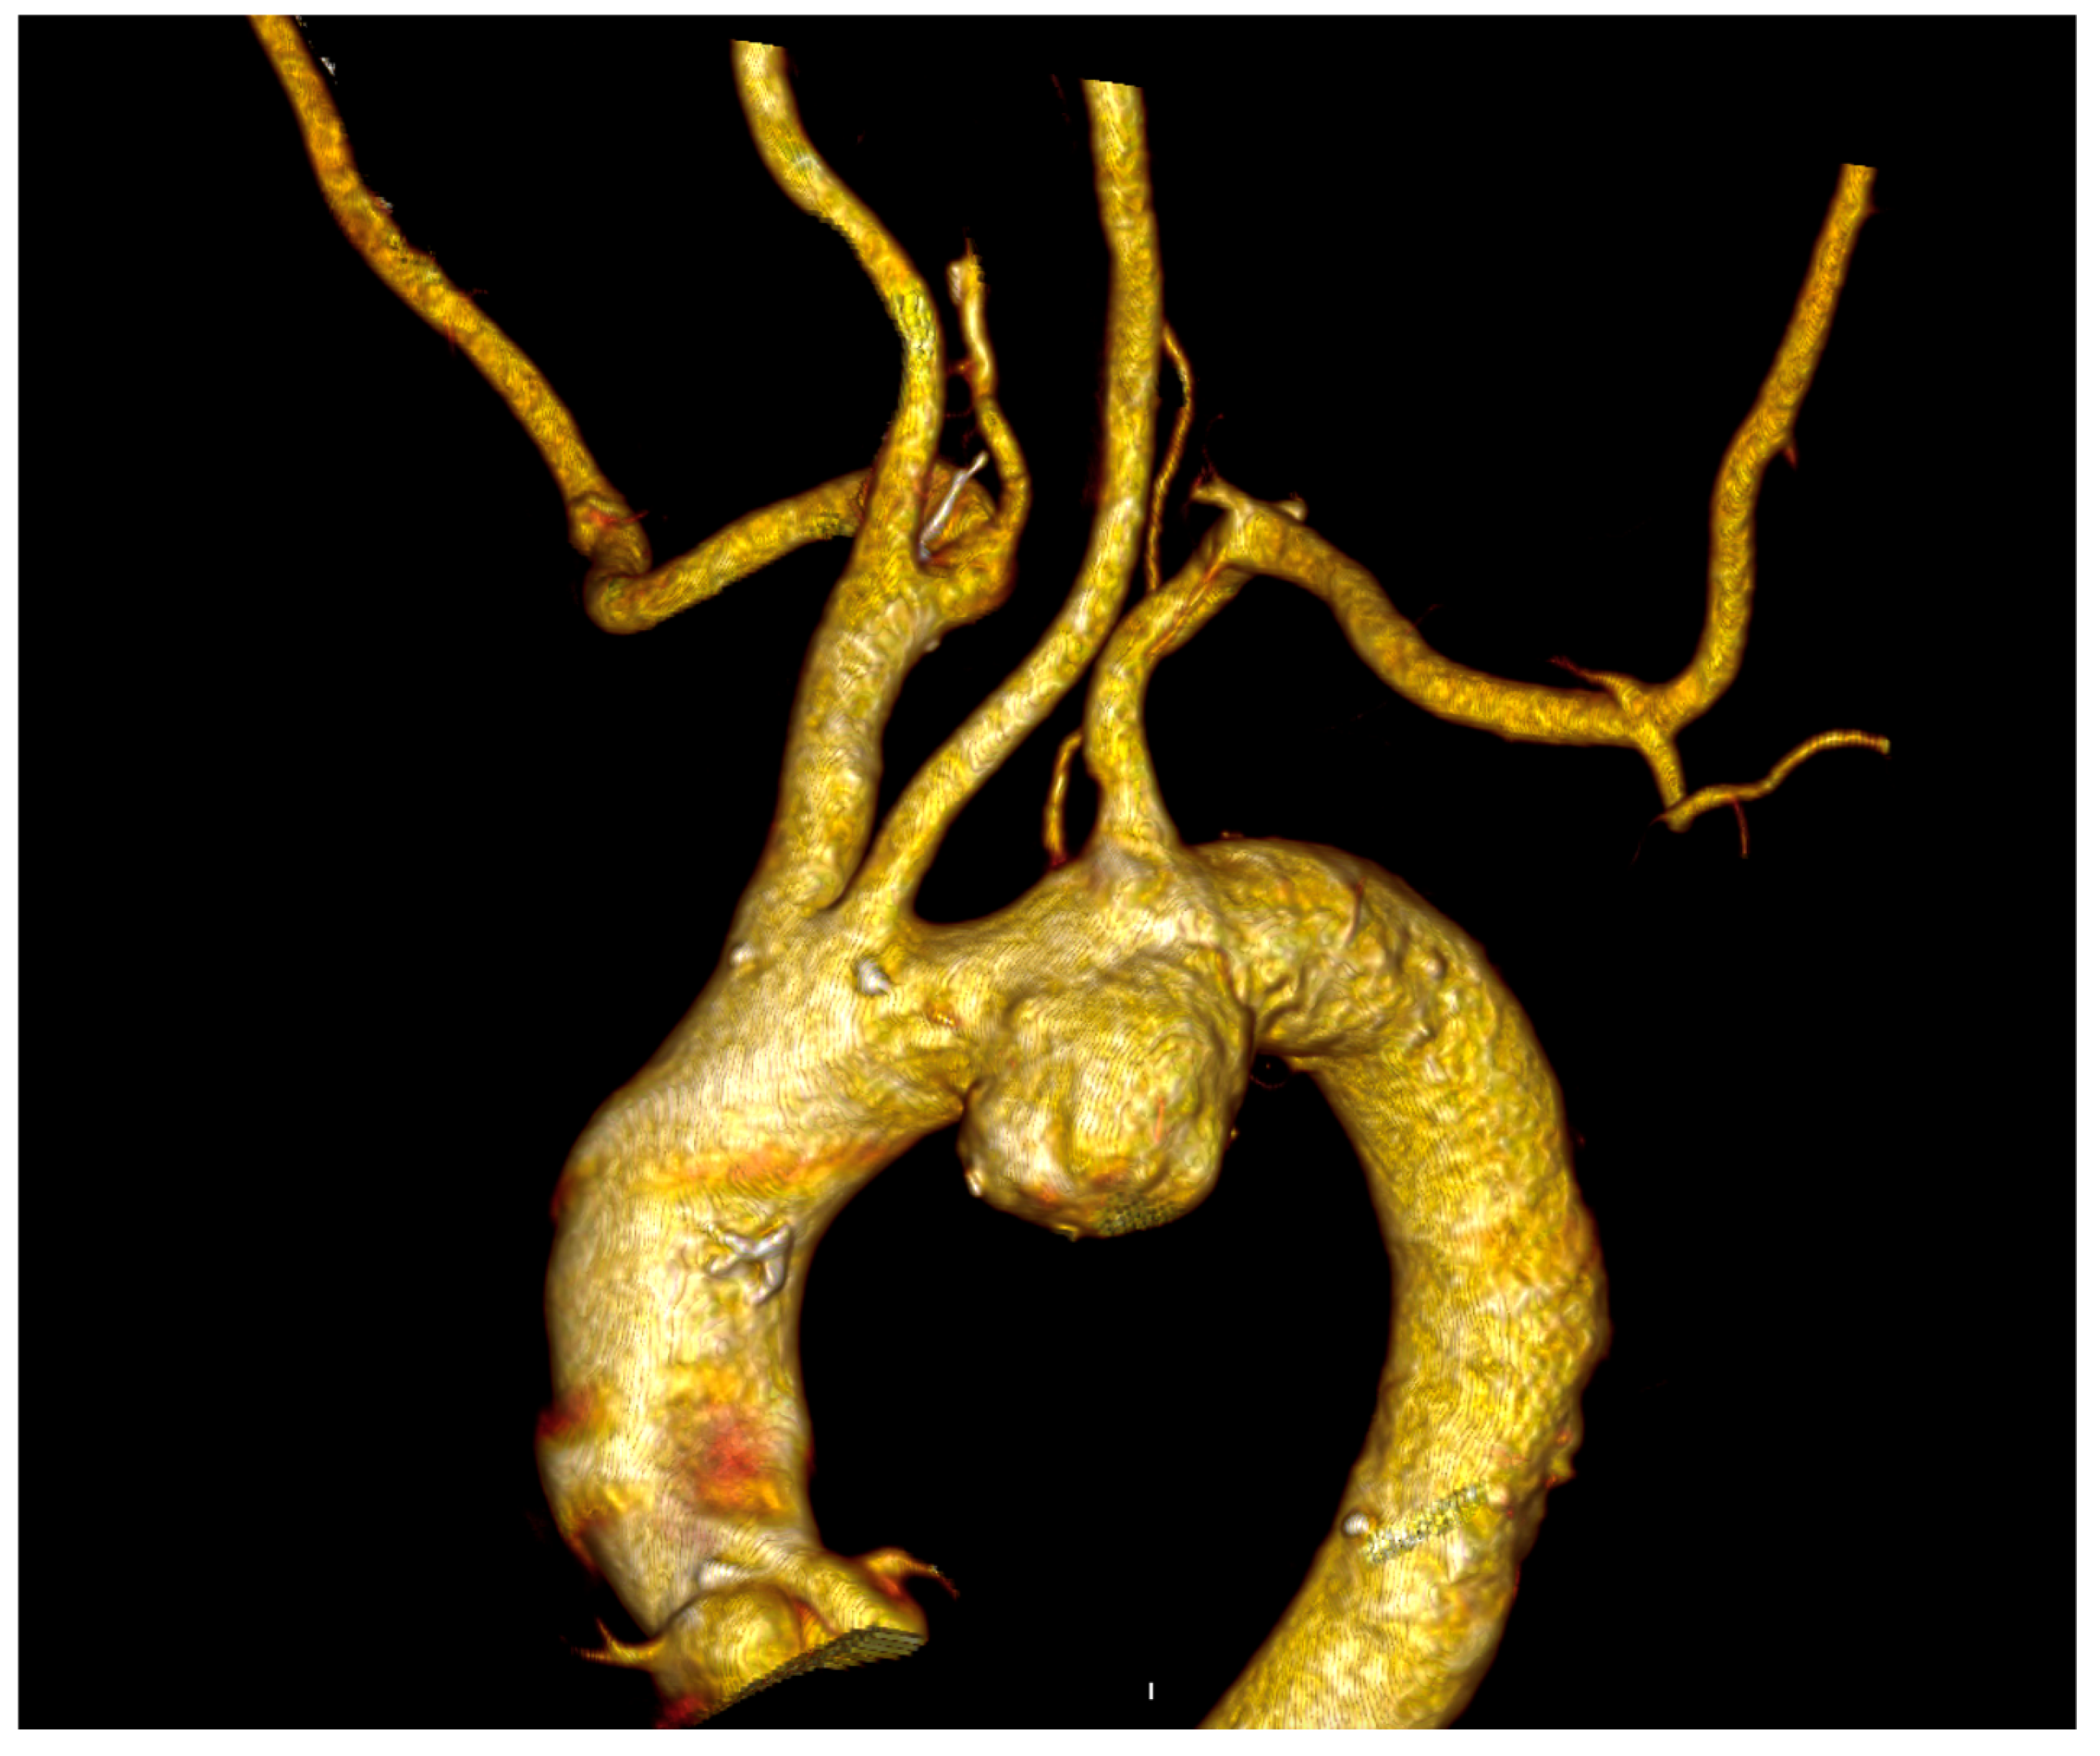

In all cases, the ILVA was detected on the preoperative computed tomography angiography (CTA) (Figure 2).

Figure 2. Preoperative Computed Tomography Angiography of a patient with a left vertebral artery arising directly from the aortic arch and affected with an aortic arch aneurysm treated at our institution.